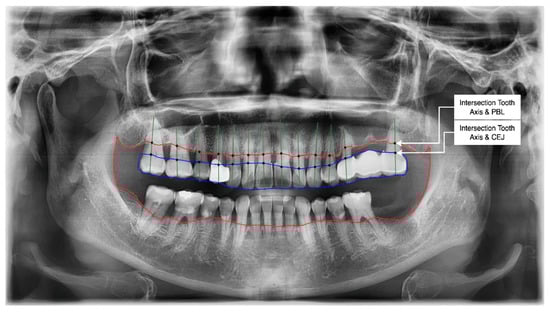

- Get the intersection of the PBL’s upper side and the tooth’s middle axis.

- Get the intersection of the CEJ’s upper side and the tooth’s middle axis.

- Calculate the length from those two intersections (known as the RBL length).

- Calculate the RBL percentage from the RBL length and tooth root.

3.2. PBL and CEJ Boundary Detection through U-Net

3.4. Determination of Tooth Stage through U-Net and YOLOv5 Integration